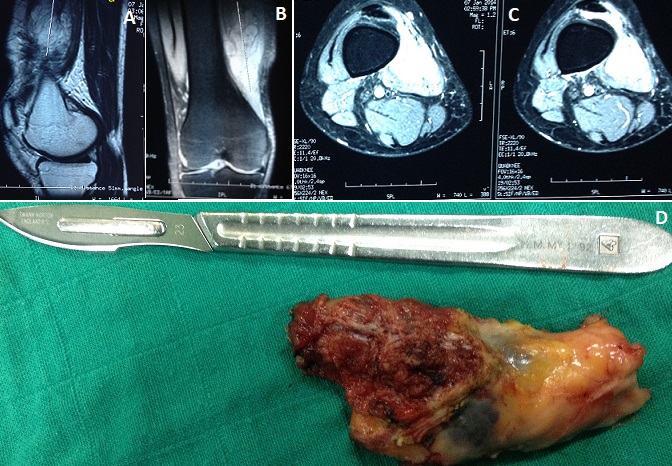

L'hémangiome est une malformation vasculaire encore appelée angiome immature. Il s'agit d'une prolifération de capillaires immatures et de cellules épithéliales. Ce sont des tumeurs vasculaires bénignes mais potentiellement graves selon le siège, dont la localisation musculaire est rare. Une jeune femme de 46 ans était adressée à la consultation, pour l'apparition d'une masse douloureuse, localisée à la partie inféro-interne de la cuisse droite. L'évolution a été marquée par l'augmentation progressive de la taille depuis 1 an et l'aggravation de la douleur devenant gênante de plus en plus lors des activités sportives. L'examen clinique retrouve une tuméfaction mobile, légèrement indurée à la palpation le reste de l'examen sans particularités. La radiographie standard était normale. L'imagerie par résonnance magnétique du genou droit montrant un processus lésionnel du muscle vaste interne au niveau du tiers inférieur en hyposignal T1 (A) et en hypersignal T2 (B) présentant une extension intra articulaire au niveau de la bourse sous quadripitale rehausse de façon importante et hétérogène après injection intraveineuse du produit de contraste (C) évoquant un angiome musculaire. Après exérèse totale l'anatomo-pathologiste a confirmé la nature de la tumeur.